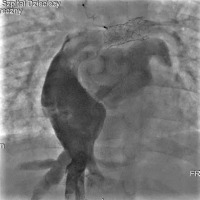

The subsequent heart catheterisation revealed a typical aorta without significant collateral vessels to the lungs. The innominate vein measured 8 mm in diameter, with no notable veno-venous anastomoses. The RPA measured 8.1 mm, while the LPA was approximately 8.5 mm in diameter and had undergone stent re-dilatation to 10 mm. The Fontan tunnel was dilated to about 3 cm, and the fenestration with a stent showed right-to-left shunting (Figure 4). Haemodynamic data showed a superior vena cava pressure of 20 mm Hg (oxygen saturation of 68%) and an IVC pressure of 22 mm Hg (oxygen saturation of 57%). The mean Fontan tunnel pressure was 20 mm Hg, and right ventricular pressures were 75/15 mm Hg. The RPA pressure was 20 mm Hg (oxygen saturation of 65%), while the LPA pressure was 18 mm Hg (oxygen saturation of 68%). The mean left atrial pressure was 16 mm Hg, with an oxygen saturation of 95%. The aortic pressure was 85/52 mm Hg, with an oxygen saturation of 85%. The calculated Qp : Qs ratio was 0.79, indicating reduced pulmonary flow. PVR was 3.8 Wood units (PVR index 2.28 Wood units·m²), and SVR was 38.13 Wood units, indicating significant haemodynamic strain typical of failed Fontan physiology.

Figure 4

Angiography of the pulmonary arteries and Fontan tunnel. The right pulmonary artery measured 8.1 mm and was dilated with the 12 mm balloon, and the left pulmonary artery had undergone stent re-dilatation to 10 mm. The Fontan tunnel was dilated to 3 cm in the central portion, and the fenestration with a stent showed right-to-left shunting. The hepatic veins and inferior vena cava were also significantly widened